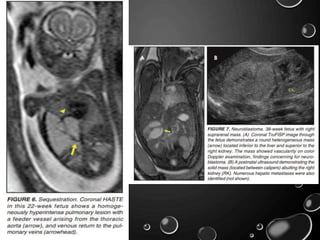

• BY MR, THE CHARACTERISTICS OF BPSS ARE SIMILAR TO

CCAMS: SOLID, T2 HYPERINTENSE MASSES, USUALLY WELL

DEFINED.

• DIFFERENTIATION BETWEEN CCAM AND INTRATHORACIC BPS

MAY BE CHALLENGING, BUT IDENTIFICATION OF A SYSTEMIC

ARTERIAL SUPPLY, MOST COMMONLY THE AORTA, INDICATES

A DIAGNOSIS OF SEQUESTRATION.

• THE DIFFERENTIAL DIAGNOSIS OF AN EXTRALOBAR

SUBDIAPHRAGMATIC BPS INCLUDES ADRENAL HEMORRHAGE

AND NEUROBLASTOMA

- SEQUESTRATIONS OCCUR MORE OFTEN ON THE LEFT

AND PRESENT AS SOLID MASSES WITH SYSTEMIC BLOOD

SUPPLY, WHEREAS NEUROBLASTOMAS OCCUR MORE OFTEN ON

THE RIGHT SIDE.